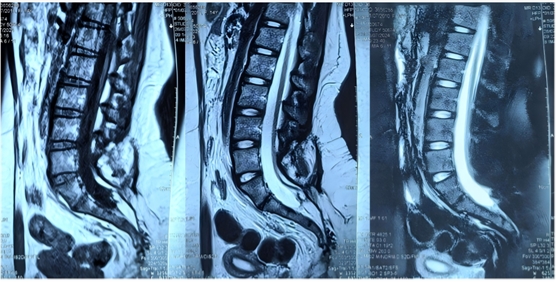

图1为1年前脊髓拴系松解术前磁共振检查片子

图2为此次手术前复查腰骶椎MR检查,提示脊髓拴系松解满意